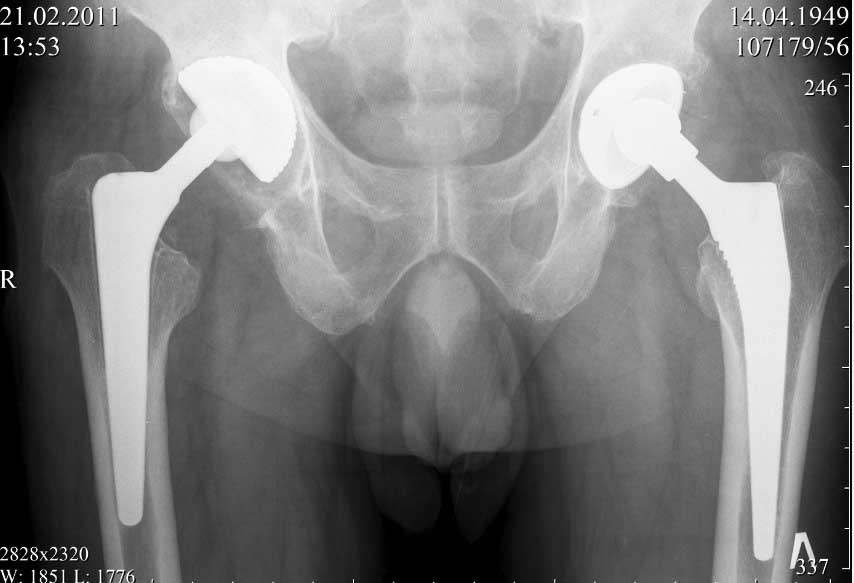

В конце 2008 года отметил боли в правой паховой области при опоре на правую ногу. На рентген снимках таза с тазобедренными суставами явных признаков нестабильности вертлужного компонента не обнаружено. В 2009 году нейрохирурги его "успешно" прооперировали на L\3-\4 связывая болевой синдром в правой паховой области с наличием грыжи указанного межпозвонкового диска. Состояние только ухудшилось, больной уже не мог долго сидеть, боль прогрессировала . Его в 2009 и 2010 годах смотрел ортопед, делались рентгенснимки, но почему то приходили к выводу что эндопротез справа стабилен. В марте 2011 года я впервые увидел его, через одну неделю после этого был прооперирован. На операции вертлужный компонент при упоре на него инструментом прокручивался во впадине и без труда был извлечен.

далее снимок в 2009 году

далее снимок у меня на приеме

На заключительных снимках явная нестабильность чашки и вероятная ножки, возможно на повторный прием придет не столь радостный (пессимистический прогноз) надеюсь, что все будет по-другому

Нет вы не поняли! Вы поспешили с выводом! Я не смог выслать окончательный, послеоперационный снимок, по техническим причинам. Я это сделал позже, что Вы и видите ниже! Извините, если я Вас запутал!

С последним, третьим снимком он ко мне и обратился, после чего он был и прооперирован на правом тазобедренном суставе!

В дополнение к моему вышеуказанному пациенту. Досылаю послеоперационный снимок, который я не выслал сразу.